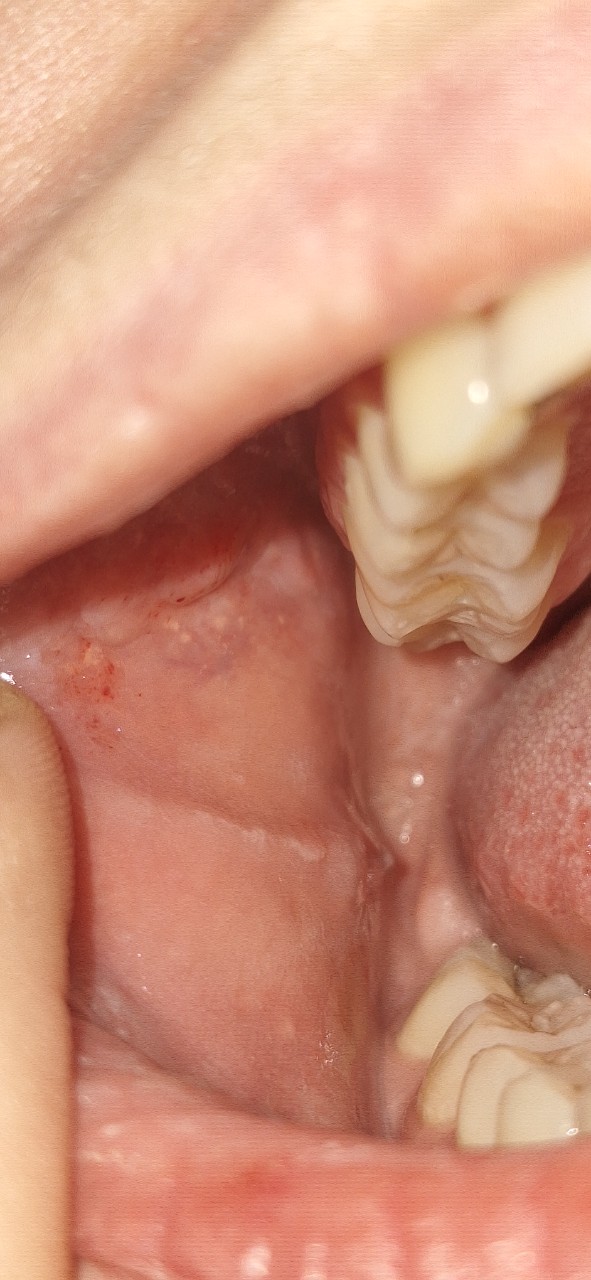

"Здравствуйте, подскажите пожалуйста, что это может быть на щеке? " - Там много чего есть. Желтые пятнышки — сальные железы, так называемые гранулы Фордайса. Есть красные точки — предположительно, из-за вредной привычки подсасывать щеку к зубам. По этой же причине можно увидеть так называемую "белую линию щеки".

Да, забыл добавить, там еще свисает, как сосочек — это место на слизистой щеки, где открывается устье выводного протока околоушной слюнной железы.

"Подскажите пожалуйста, на фото как сосочек или отросток с сосудиком внутри, это норма или что-то страшное? " - Ничего страшного. Все нормально.